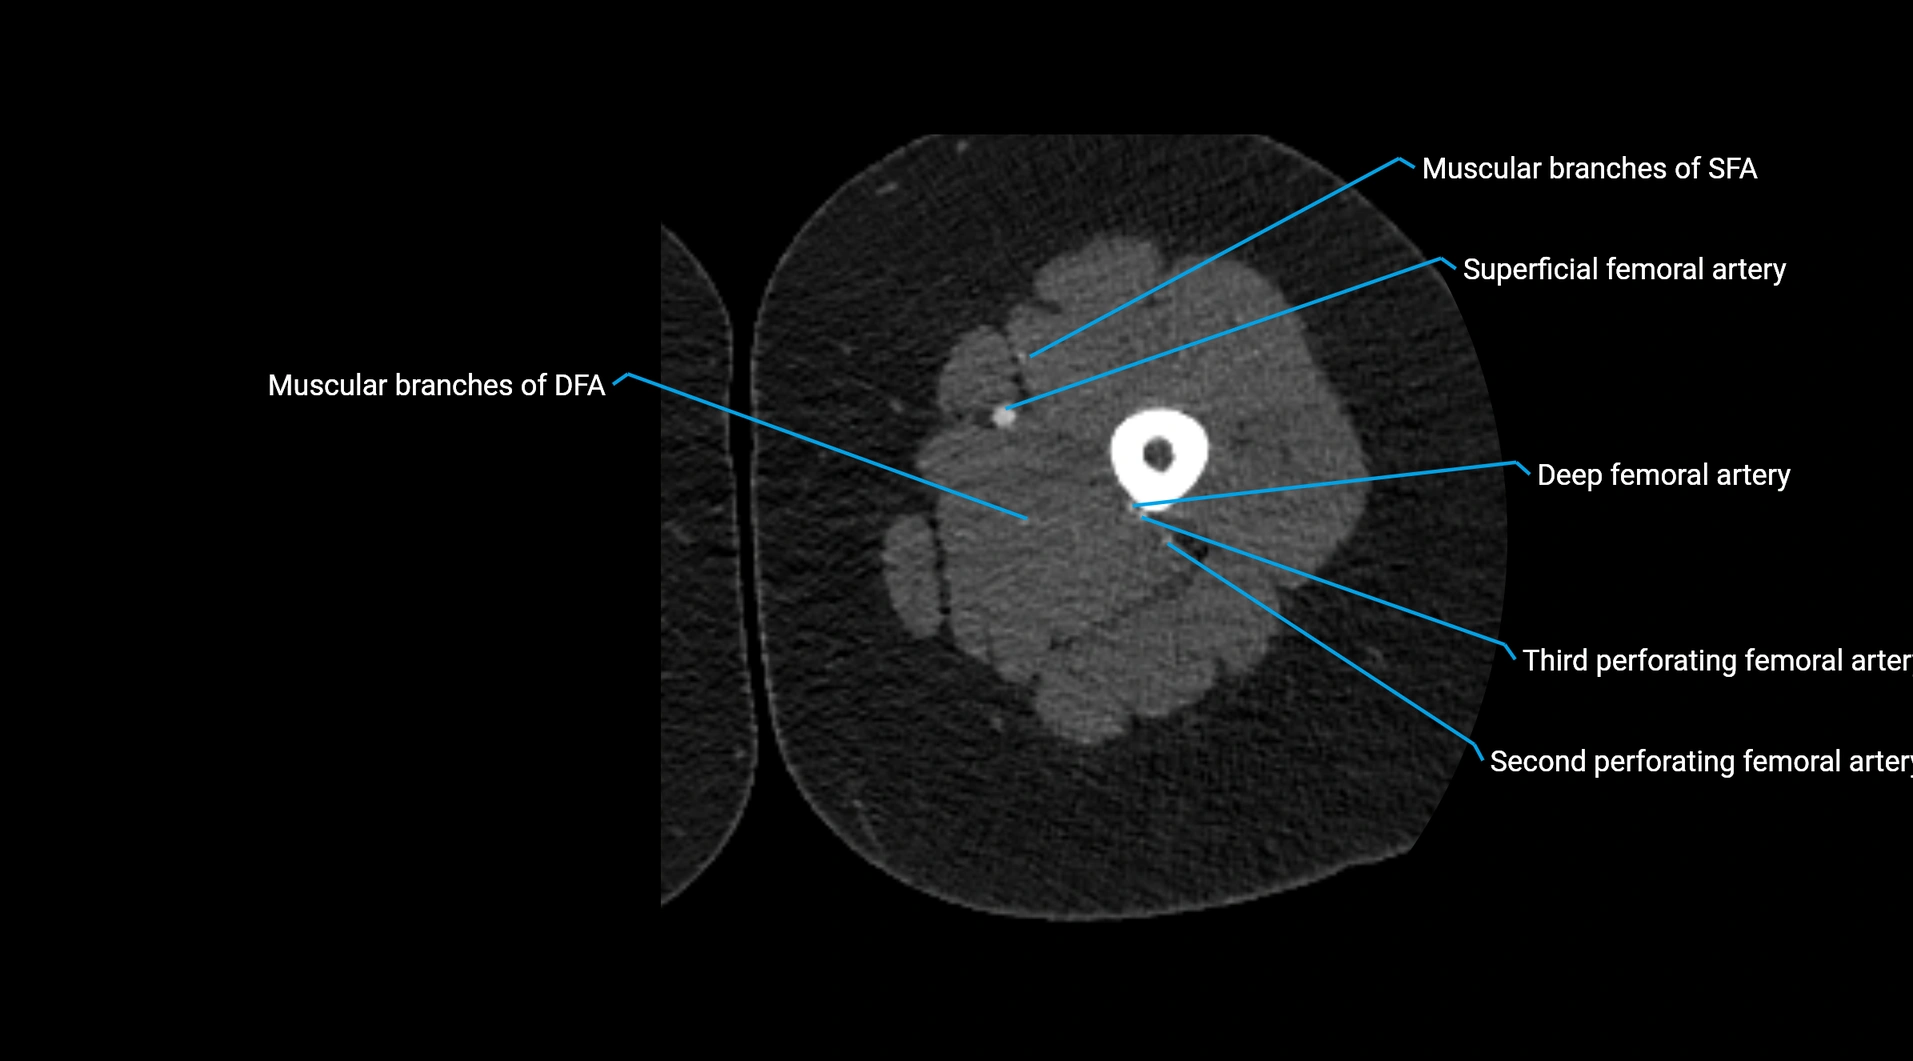

CT images

image